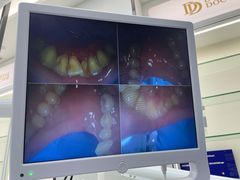

• -牙博士口腔品牌连锁(杨浦店)

夏日莫莫茶 | 21-08-13